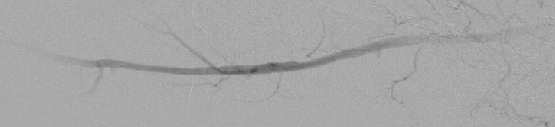

There is growing interest in CO2 digital subtraction angiography as an alternative to traditional angiography. Injection of this CO2 gas with its decreased radiodensity creates radiographic contrast by transiently displacing blood from the artery one is imaging. Carbon dioxide is 20 times more soluble in blood than oxygen and dissolves rapidly by elimination through the lungs during normal respiration.25,26 Intravascular CO2 produces no allergic reaction and causes no nephrotoxicity (see photo at left).

Madhusudhan and colleagues studied 21 consecutive patients (with ages ranging between 29 to 79 with a mean of 48 years) with 27 angiograms (15 unilateral, six bilateral), using both iodinated contrast media and then CO2 as contrast agents during a 15-month period.27 All patients clinically suffered from calf or gluteal claudication and nine patients also had rest pain. The researchers also included patients in the study who had either ischemic foot ulcers or gangrenous changes in the limb.

Of the 195 major named arteries evaluated (common, external and internal iliac, superficial and deep femoral, popliteal, and anterior and posterior tibial), the use of iodinated contrast media opacified 188 (96.4 percent) arteries and CO2 opacified 168 (86.2 percent) arteries. This excluded segments that were not adequately opacified either due to the presence of arterial sheath or complete proximal occlusion. A total of 113 arterial segments of 27 limbs had two evaluations each. Researchers gave a score of 0, 1 or 2 for non-visualization of collaterals, visualization of few collaterals and visualization of many collaterals respectively. Madhusudhan and coworkers found that both techniques graded 180 (79.7 percent) segments the same. Iodinated contrast media evaluated 35 (15.5 percent) segments better and CO2 digital subtraction angiography demonstrated 11 (4.9 percent) segments more clearly.27

Overall, one can obtain appropriate opacification of the iliac and femoral arteries via CO2 angiography and treating physicians should consider CO2 as the initial contrast agent for the evaluation of PAD in patients with renal failure and iodine contrast allergy. If there is inadequate depiction of a vessel despite selective injection, one may supplement this with some amount of iodinated contrast media for better visualization if indicated at that time.